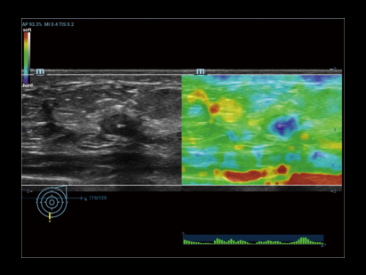

V-Flow

Векторный анализ кровотока в сосудах — это подход к оценке сосудистой гемодинамики, используя цветовой векторный анализ скорости движения и направления в каждой точке кровотока.